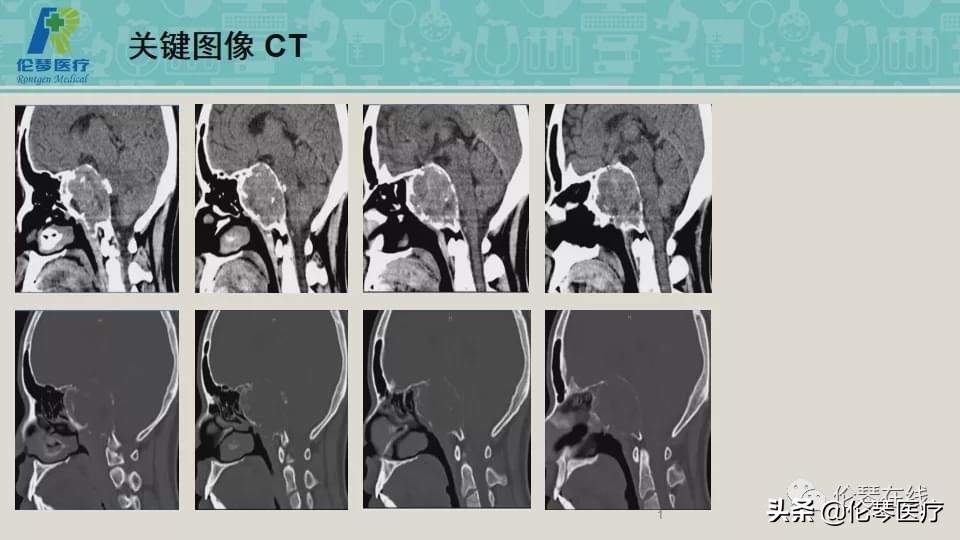

年龄:21岁

主诉:头痛,双眼内收、外展受限8个月,加重2月

检查:CT扫描(影像图像见下方)